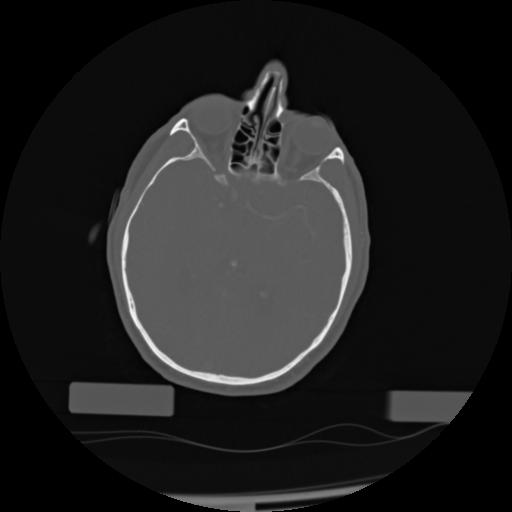

21 ANGIO,CE,Axial,3.0,ANGIO,,